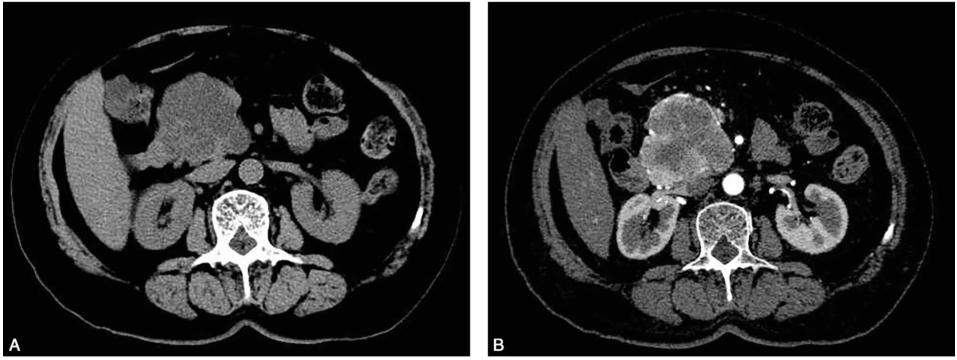

胰腺增强CT(图1)示胰头钩突部一团块状低密度灶,最大直径约6.8cm,大部分为液体样低密度,增强扫描可见病灶内大量细密分隔呈明显不均匀强化,并见迂曲穿行的肿瘤血管。

图1 胰腺增强CT

A.平扫;B.动脉期;C.门脉期。